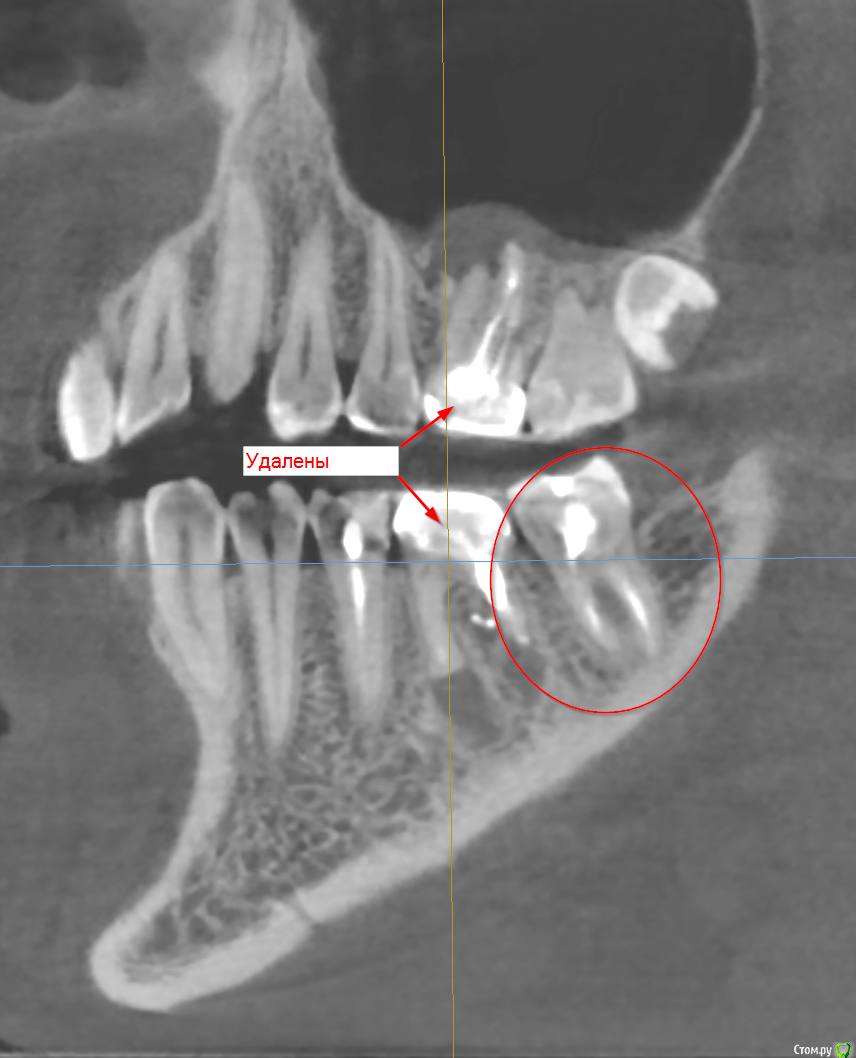

tmporaries Опубликовано 22 марта, 2018 Поделиться Опубликовано 22 марта, 2018 (изменено) Удалять или нет нижний дальний зуб?(Выделен на снимке) Изменено 22 марта, 2018 пользователем tmporaries Ссылка на комментарий

Борис80 Опубликовано 23 марта, 2018 Поделиться Опубликовано 23 марта, 2018 последний снимок очень явно намекает на наличие перфорации в области бифуркации корней и очаг разрежения, шансы сохранить зуб равны практически нулю. В общем и целом при вашей ситуации я за удаление Ссылка на комментарий

Гарриевич Опубликовано 24 марта, 2018 Поделиться Опубликовано 24 марта, 2018 Если есть желание зуб сохранить, то проводится ревизия и по факту ревизии принимается решение. Если такового желания нет, то Удаление Ссылка на комментарий